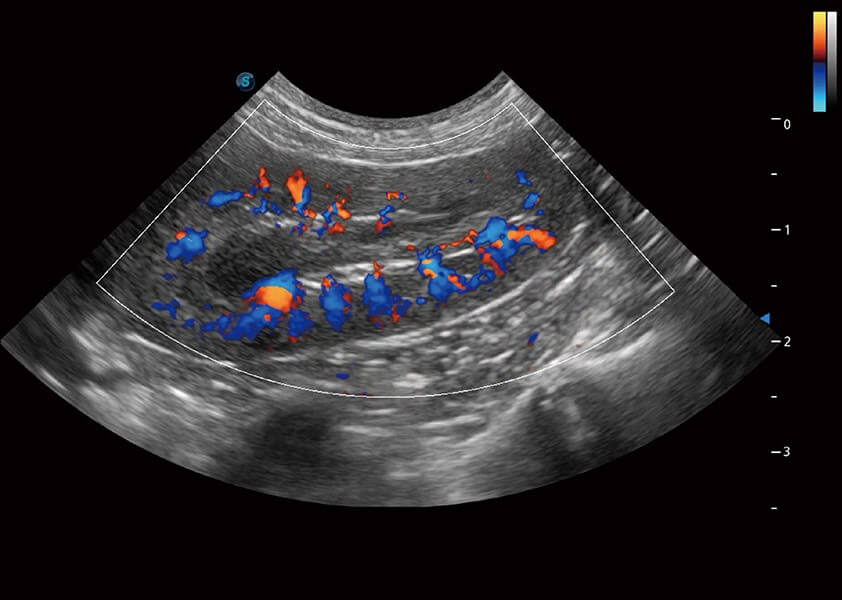

(犬)肾脏血流